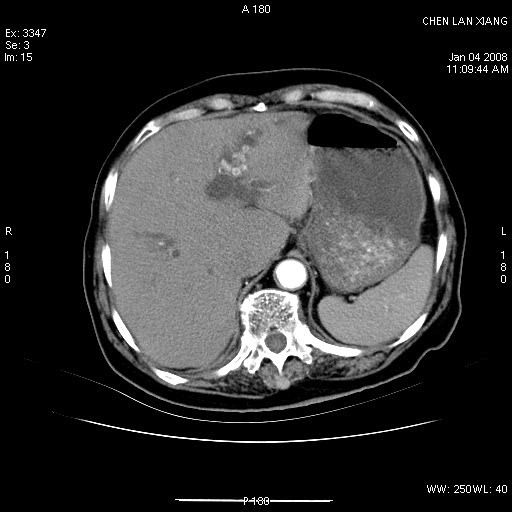

标题: CT11180:女,76岁,腹痛3-4天 [打印本页]

标题: CT11180:女,76岁,腹痛3-4天

女,76岁,腹痛3-4天,b超示:肝内实性肿物,胆囊强回声,胆总管扩张.

1 胆总管末端结石伴肝内胆管结石,肝内外胆管扩张。2 胆囊扩大,胆囊壁不规则增厚,内见软组织密度影。考虑:慢性胆囊炎,不除外胆囊癌!

胆总管末端结石伴肝内胆管结石,肝内外胆管扩张。低位胆道梗阻2 胆囊扩大,胆囊壁不规则增厚,内见软组织密度影。考虑:慢性胆囊炎,不除外胆囊癌!

胆囊内结增强影,肝内胆管、胆总管扩张明显。肝内胆管、胆总管下段多发结石,胆囊癌,建议mrcp检查

胆囊密度增高,增强后周边肝组织及胆囊窝下部周边软组织延时性不规则强化.然胆囊壁未见明显不规则增厚及肿块.左侧肝内胆管及胆总管下段结石伴胆系扩张.

考虑;胆囊炎(黄色肉芽肿性胆囊炎?),左侧肝内胆管及胆总管下段结石.

ct所见:1、 肝内胆管结石,肝内外胆管扩张。低位胆道梗阻,胆总管下端结石;2 胆囊扩大,胆囊壁不规则增厚

考虑:胆总管下端结石并肝内外胆管扩张,肝内胆管结石;

慢性胆囊炎